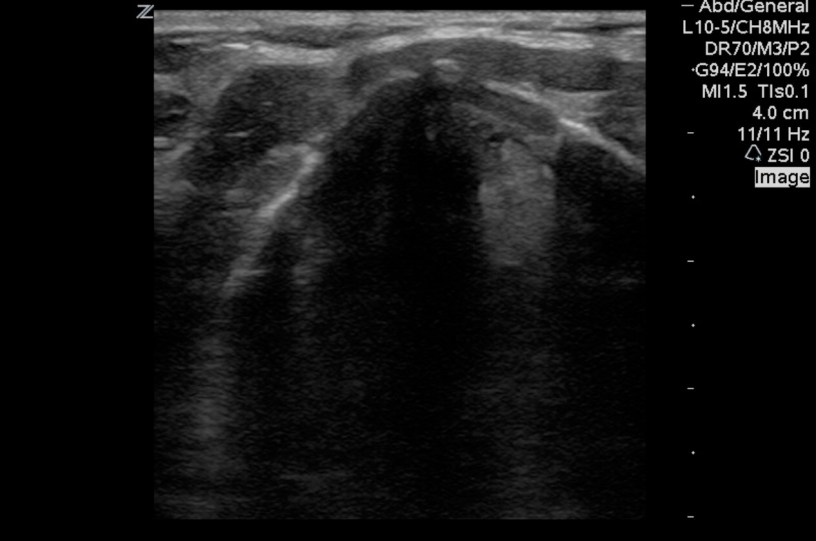

Sono Instruction, sono of the week